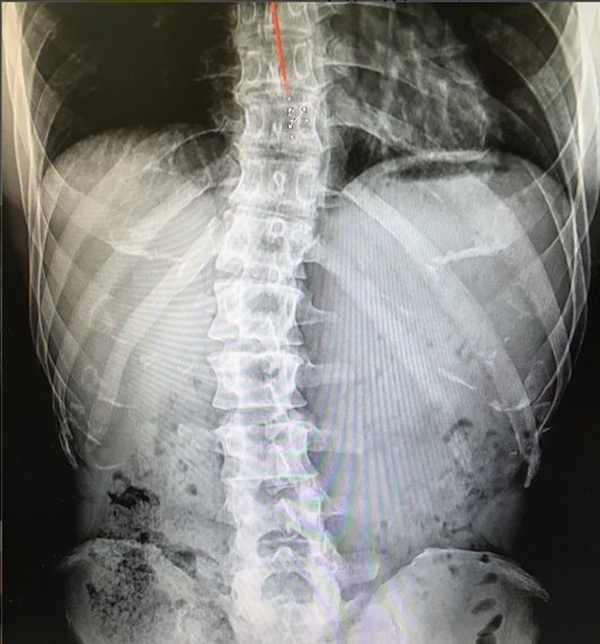

가수 김종국이 군복무 관련 악플에 입을 열었습니다. 자신의 척추를 촬영한 엑스레이 사진도 공개했는데요.

김종국은 4일 오후 자신의 인스타그램을 통해 엑스레이 사진을 공개했습니다. 정상인보다 훨씬 휘어진 모습이었는데요.

그는 고등학생 때 허리 통증을 느껴 쓰러졌고, 척추측만증이라는 진단을 받았습니다. 가만히 있어도 극심한 고통을 느낄 정도였죠.

고등학교 때 처음 허리 통증으로 쓰러졌을 때부터 쭉 가지고 있던 척추측만증.

이런 허리로 어떻게 그런 몸을 만들죠 한다. 난 만들었다 아니 만들고 있다. 이 휘어진 척추 뭔가로는 잡아줘야 하니까.